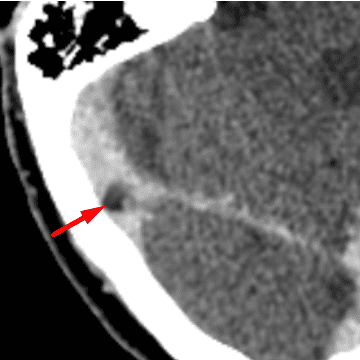

Arachnoid Granulation

Case 20